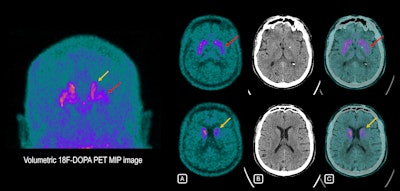

46-year-old man with involuntary tremors and muscular stiffness in right upper and lower limb. He was referred due to loss of sense of smell (anosmia), which started more than 10 years previously. Electromyography was normal, but mild cognitive impairment was apparent. Brain F-18 DOPA PET scan shows decreased tracer uptake in left putamen (red arrows) and, to a lesser extent, in the left caudate nucleus (yellow arrow), reflecting dopamine pathway deficiency, compatible with early onset Parkinson's disease. Right striatum with normal typical “comma shape” uptake. (A) PET images. (B) CT images. (C) Fused PET/CT images. All figures courtesy of Dr. Magali Hovsepian et al and presented at ECR 2025.